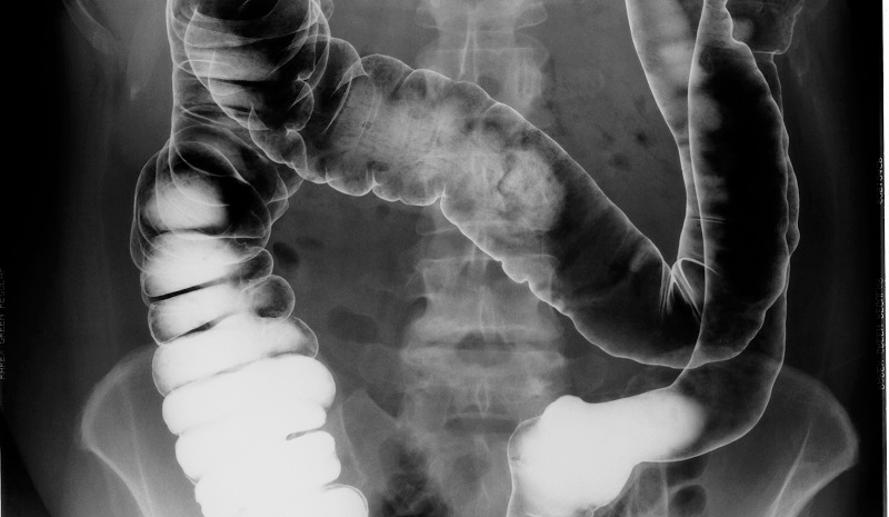

사진: 게티이미지뱅크